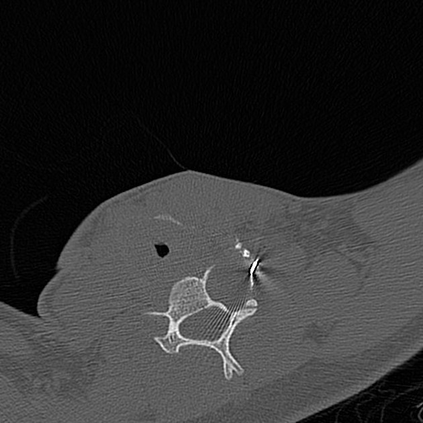

In this study, we aim to initiate the development of Radiology Foundation Model, termed as RadFM.We consider the construction of foundational models from the perspectives of data, model design, and evaluation thoroughly. Our contribution can be concluded as follows: (i), we construct a large-scale Medical Multi-modal Dataset, MedMD, consisting of 16M 2D and 3D medical scans. To the best of our knowledge, this is the first multi-modal dataset containing 3D medical scans. (ii), We propose an architecture that enables visually conditioned generative pre-training, allowing for the integration of text input interleaved with 2D or 3D medical scans to generate response for diverse radiologic tasks. The model was initially pre-trained on MedMD and subsequently domain-specific fine-tuned on RadMD, a radiologic cleaned version of MedMD, containing 3M radiologic visual-language pairs. (iii), we propose a new evaluation benchmark that comprises five tasks, aiming to comprehensively assess the capability of foundation models in handling practical clinical problems. Our experimental results confirm that RadFM significantly outperforms existing multi-modal foundation models. The codes, data, and model checkpoint will all be made publicly available to promote further research and development in the field.